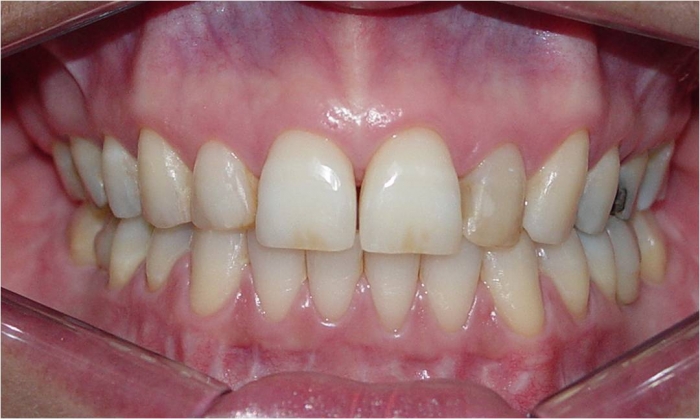

Sorriso final

Mordida final